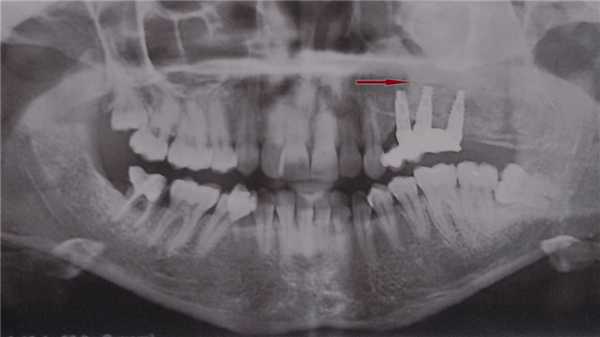

о Панорамная рентгенография

(Слева) На панорамной рентгенограмме определяется зрелая ЦКД, приводящая к вздутию задней стенки верхней челюсти слева. Патологический очаг распространяется также в верхнечелюстную пазуху, приподнимая ее дно.

(Справа) На аксиальной КТ в коаном окне у этого же пациента определяется двухстороннее поражение с вздутием задних наружных краев верхне-челюстных пазух. Рентгеноконтрааные очаги зрелой ЦКД частично заполняют верхнечелюстные пазухи, приводя к снижению их пневматизации. Обратите внимание на относительную симметричность поражений.